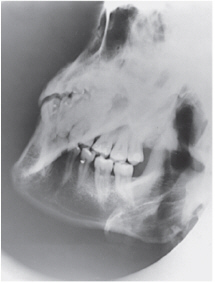

parietoacanthial (waters)

which of the following must be projected below the maxillary sinuses for the parietoacanthial projection (waters method) of the sinuses

petrous pyramids

which projection best demonstrates the maxillary sinuses

where are the petrous ridges seen on an accurately positioned image of the parietoacanthial waters method projection of the paranasal sinuses

inferior to the floor of the maxillary sinuses